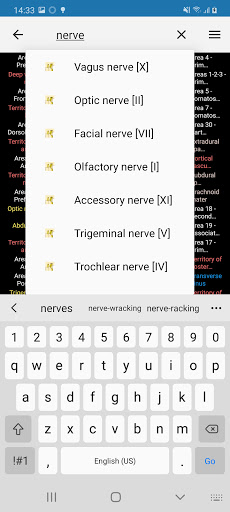

* اعثر على الأجزاء التشريحية الخاصة بك بسهولة أكبر بفضل ميزة البحث الجديدة والأكثر سهولة وقوة

* تحسين أداء البحث عن البنية التشريحية